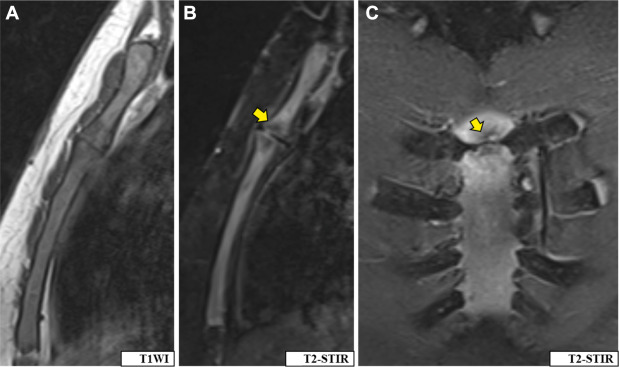

➤治疗6个月复查MRI:骨髓信号异常范围缩小,强化程度降低,T2/STIR序列出现低信号区(提示骨质硬化及病变愈合)(图3);

➤治疗2年疗程结束:患者无残余症状,无功能受限;末次影像学检查显示骨髓水肿完全消退,可见骨质硬化改变(提示病变愈合)。

图3-抗结核治疗6个月后MRI:T1加权像(A)、T2-STIR加权像(B、C)显示骨髓T2/STIR高信号范围缩小(B、C),强化程度降低(箭头),出现T1/T2/STIR低信号区(箭头),提示骨质硬化。